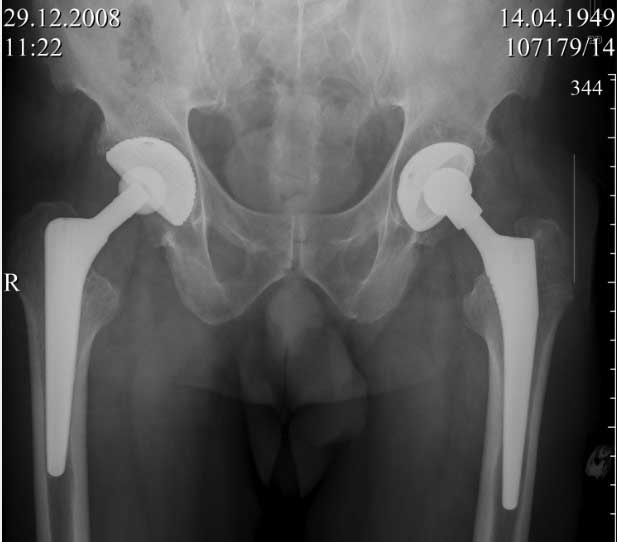

ниже снимок в 2008 году